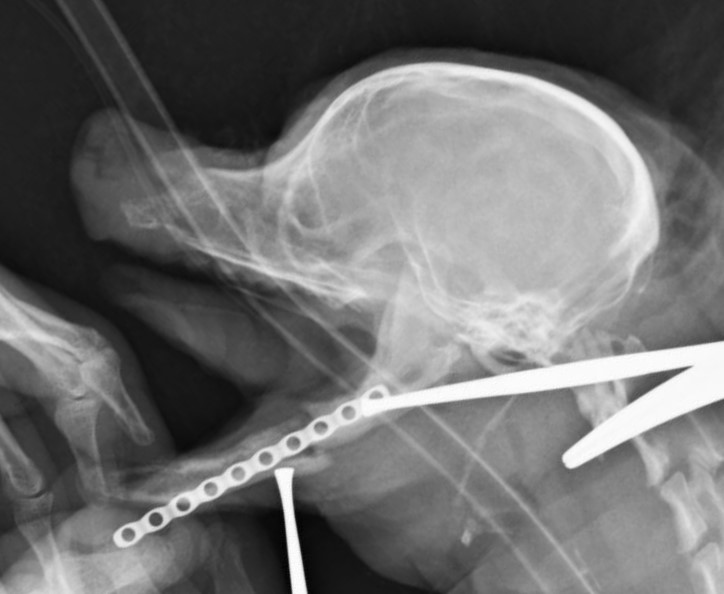

重度の歯周病で両側の下顎の病的骨折をしているワンちゃんが来院されました。悪い歯の抜歯と下顎のプレート固定(TITAN LOCK1.2mm使用)で対応しました。退院後しっかりご飯が食べられるようになりました。よかったね。